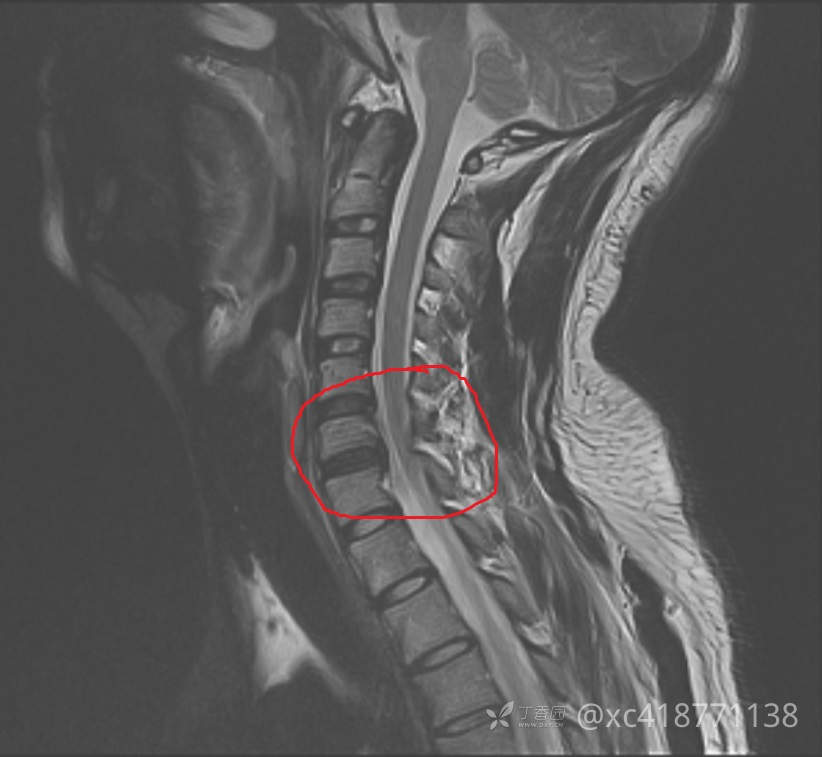

辅助检查:入院查心电图、胸片示正常。腹部+泌尿系B超示脂肪肝。双肾CT示:右肾小结石。附见:L5椎体I°滑脱,双侧椎弓峡部裂,隐裂。颈椎MRI示:2023-01-18 颈椎磁共振平扫(1.5T),颈椎退行性改变:骨质增生;黄韧带稍增厚。椎间盘变性伴C3/4-C6/7椎间盘不同程度膨、突出,双侧神经根受压,椎管稍狭窄,伴颈髓略受压,C4-6左侧神经根T2WI信号稍增高,结合临床。2023-01-18 左肩关节磁共振平扫(1.5),1、左肱骨头关节面下少许骨损伤。2、左侧肩袖前上份损伤,冈上肌、肩胛下肌腱损伤,伴肩袖周围渗出。3、左肩关节肱二头肌长头盂唇复合体(SLAP)损伤可能,结合临床。4、左肩关节下关节囊增厚,考虑慢性损伤可能。5、左三角肌下滑囊及喙突下囊少许积液。6、左肩锁关节炎?。2023-01-17 胸部正侧位,两肺、心膈未见异常。

临床诊断: 疾病诊断:1.颈部脊髓损伤(左侧C4)2.左臂丛神经损伤3.左肩袖损伤4.左肾结石。功能诊断:1.左上肢运动障碍2.颈部、左肩部及上肢疼痛3.日常生活大部分自理